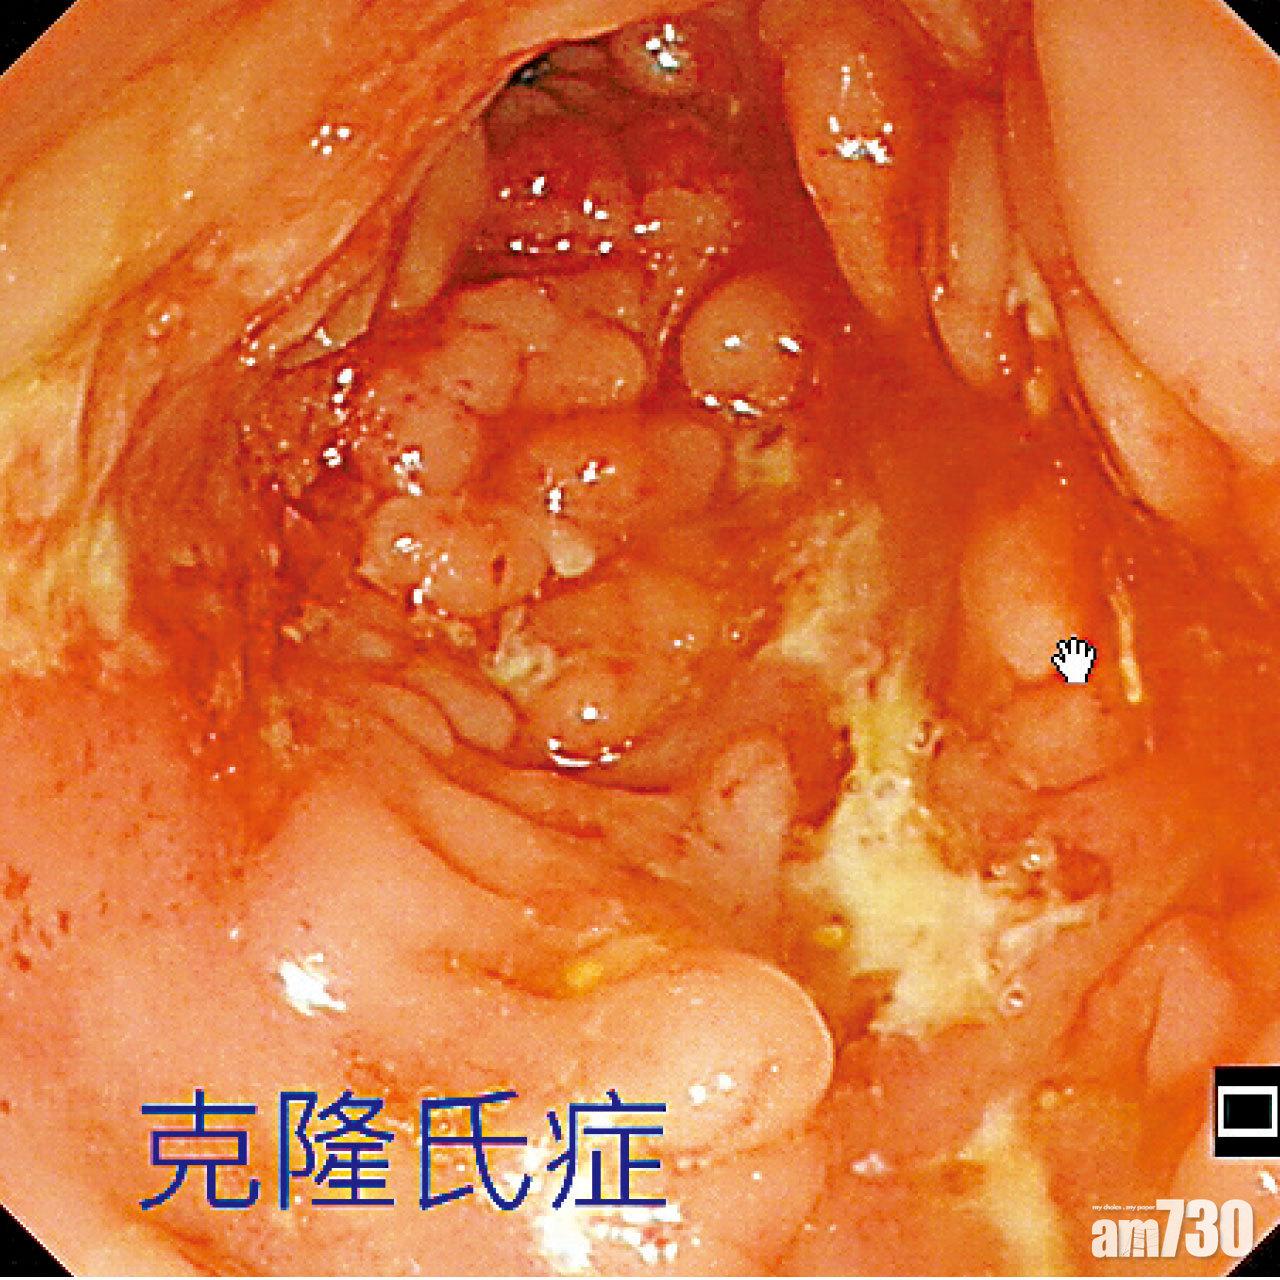

他指出,此病分克隆氏症和潰瘍性結腸炎兩種:前者影響由口腔、食道、胃、大小腸至肛門整個消化系統,併發症除了腸道閉塞、肛裂,更會有瘺管,即糞便從肛門周邊、陰道或皮膚滲漏出來,對患者社交生活造成嚴重困擾;後者則主要影響大腸,患者常有「裡急後重」,即急著大便卻只排出小量,但事後仍有便意,嚴重時可併發巨結腸症、腸道破裂和腹膜炎。

▲克隆氏症腸道內壁